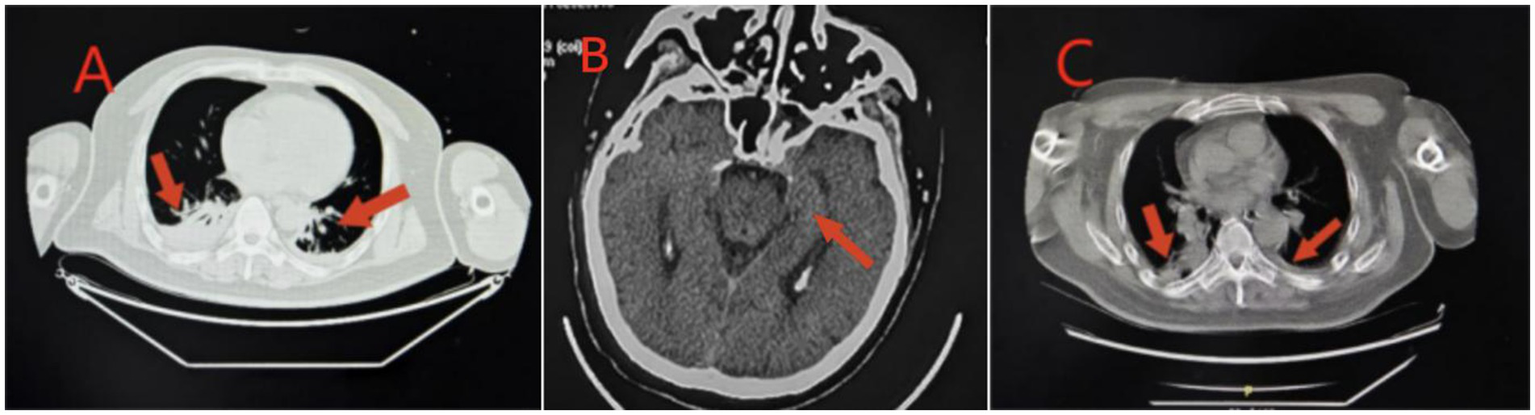

Figure 4

Imaging findings in Case 3: Panel (A) Lung CT shows inflammation in the lower lobes of both lungs, which is more prominent on the right side; Panel (B) Re-examination of brain CT shows ischemic degenerative foci in the bilateral basal ganglia and corona radiata; Panel (C) Lung CT shows inflammation in both lungs, and inflammation in the upper lobe of the right lung.

Case 3 was a 52-year-old man with no previous health issues. He was admitted to the hospital on February 8, 2025, presenting with loss of consciousness and respiratory failure. Physical examination showed a temperature of 36.9 °C, heart rate of 89 beats/min, respiratory rate of 23 breaths/min, blood pressure of 142/89 mmHg, and SpO2 of 99%, revealed a state of drug-induced sedation and intubation, with coarse bilateral breath sounds and audible wet rales. Admission diagnosis: Acute poisoning; Asphyxiating gas poisoning. Laboratory and imaging results are shown in Tables 1, 2 and Figure 4. He was treated with a combination of propofol and dexmedetomidine for sedation; betamethasone and meropenem to control pulmonary inflammation; danshen polyphenols for cardiovascular protection; mecobalamin and vitamin B1 for nerve nutrition; and Xingnaojing injection combined with naloxone to improve cerebral circulation. Continuous electrocardiogram monitoring was maintained throughout the treatment. However, the patient developed refractory inflammation during his hospital stay, which could not be controlled even with the combined use of multiple antibiotics. Additionally, he repeatedly experienced convulsions and restlessness, presenting with decorticate syndrome. Despite having spontaneous breathing, he was unable to be weaned off mechanical ventilation after multiple attempts. On February 20, 2025, a tracheotomy was performed, and the tracheotomy site was connected to an invasive ventilator for assisted ventilation. On March 18, 2025, the family strongly requested to take the patient home for continued treatment at a local hospital. Follow-up by phone indicated that the patient was still receiving treatment at the local hospital.